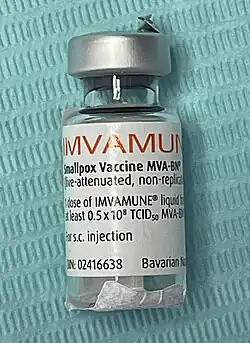

MVA-BN

MVA-BN (also known as: Imvanex in the European Union; Imvamune in Canada; and Jynneos[40][41]) is a vaccine manufactured by Bavarian Nordic by growing MVA in cell culture. Unlike replicating vaccines, MVA-BN is administered by injection via the subcutaneous route and does not result in a vaccine "take."[42] A "take" or "major cutaneous reaction" is a pustular lesion or an area of definite induration or congestion surrounding a central lesion, which can be a scab or an ulcer.[43]

MVA-BN can also be administered intradermally to increase the number of available doses.[44] It is safer for immunocompromised patients and those who are at risk from a vaccinia infection. MVA-BN has been approved in the European Union,[1] Canada,[45][46][47] and the United States.[48][49] Clinical trials have found that MVA-BN is safer and just as immunogenic as ACAM2000.[50][51][52] This vaccine has also been approved for use against mpox.[53][54][55]